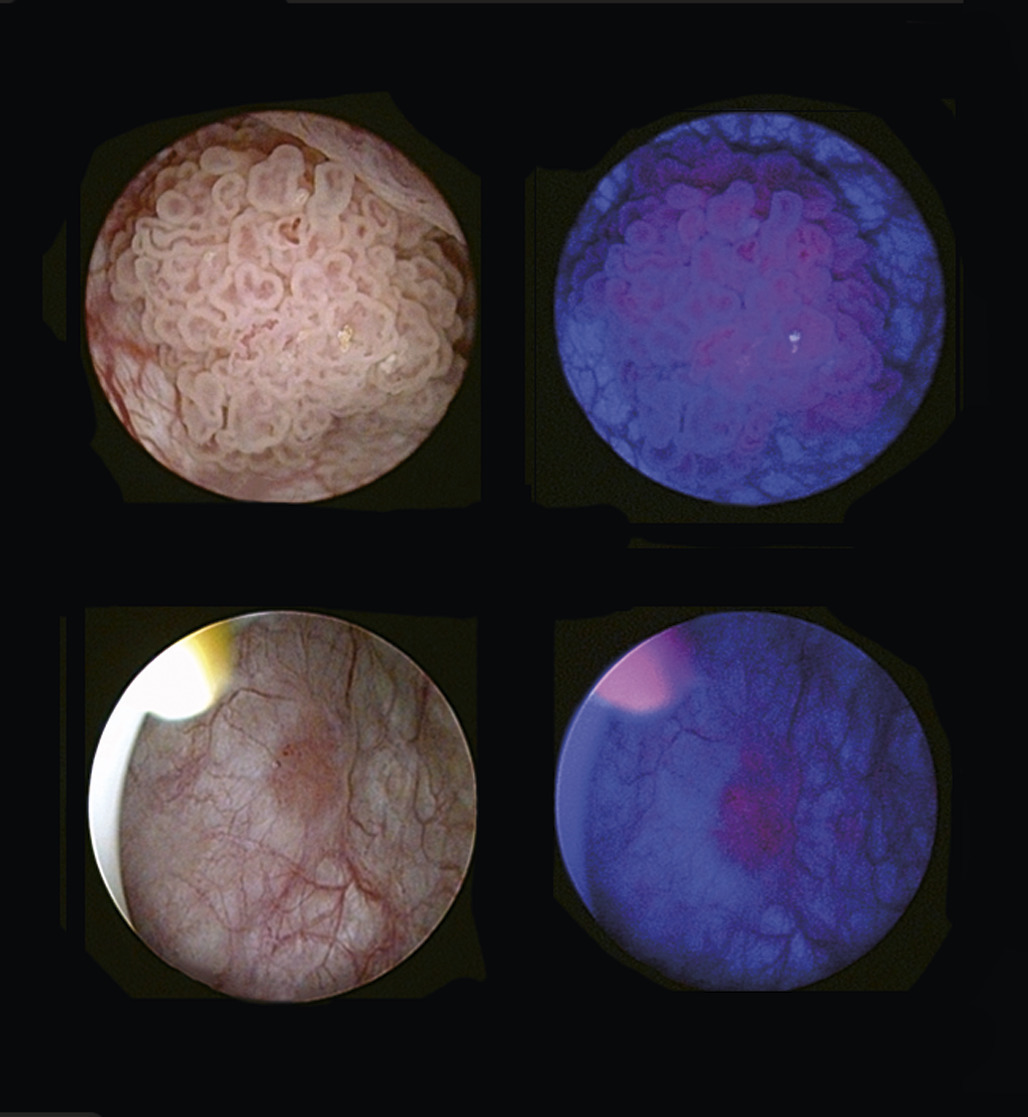

La résection peut s’accompagner d’un photodiag­nostic dynamique par fluorescence (fig. 6) permettant d’en améliorer la qualité et donc de prévenir les récidives. L’instillation intravésicale pré-résection transurétrale de vessie d’acide hexamino-lévulinate permet de faciliter le repérage des zones tumorales, notamment en cas de tumeurs planes (Cis) en rendant ces zones fluorescentes lorsque la résection transurétrale de vessie est réalisée en lumière bleue. Cette technique est recommandée dans certaines situations à risque (tumeurs multi­focales, > 3 cm, de haut grade).